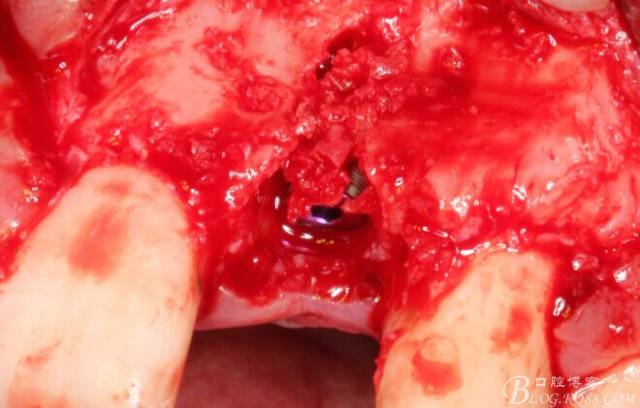

再次翻瓣。

先行粘骨膜減張,取自體血液。

根方用取骨鉆取自體骨。

旋入一長(zhǎng)兩短3顆鈦釘。

將自體骨與BIO-OOS骨粉混合植到術(shù)區(qū),蓋生物膜。

縫合。